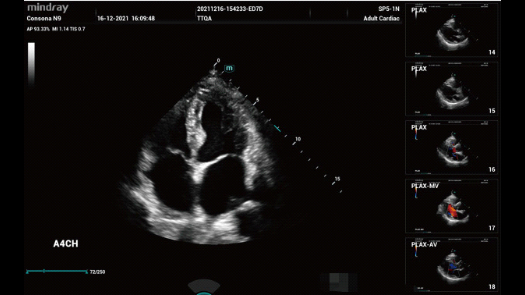

Bez wzgl?du na to, czy pracujesz w szpitalu, przychodni, czy u?ywasz ultrasonografu do badaÅ ogÃģlnych, w opiece zdrowotnej kobiet lub w badaniach sercowo-naczyniowych, w serii Consona znajdziesz bardzo pot??ne narz?dzia, aby utrzyma? si? w czo?Ãģwce.

Galeria obrazÃģw